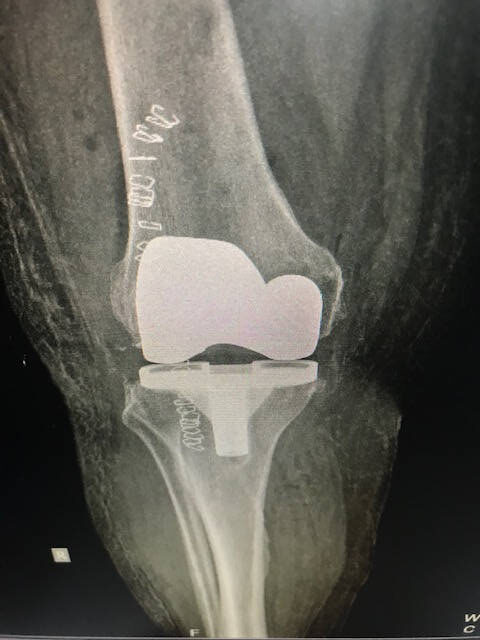

Η ομάδα της Β΄Ορθοπαιδικής κλινικής Ιασώ Θεσσαλίας, εκπαιδεύεται σε νέες τεχνικές χρήσης εξατομικευμένων προθέσεων στην ολική αρθροπλαστική γόνατος.

Πληροφορίες για την αντιμετώπιση της αρθρίτιδας γόνατος με ολική αρθροπλαστική μπορείτε να βρείτε εδώ